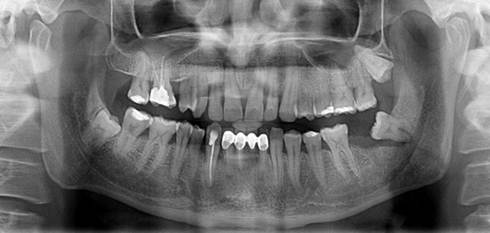

A 35-year-old female patient was admitted to the Department of Oral Surgery, Faculty of Dentistry, Istanbul University, with the complaint of mild pain in the right mandibular angle. She was systemically healthy and showed no swelling on the right side of the mandible due to infection. A panoramic radiograph revealed the presence of a mesioangular and deeply impacted mandibular right third molar surrounded by mild radiolucency. Extraction of the tooth was planned due to the pain and the radiolucency surrounding the crown and apex (Fig. 1).

Preoperative x-ray of the patient showing deeply impacted right third molar and radiolucency surrounding the tooth.